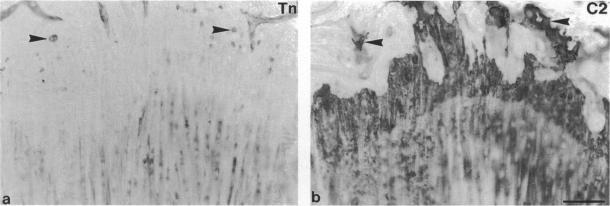

The extracellular matrix protein, tenascin, is selectively expressed in a variety of connective tissues during development. In this study, the distribution of tenascin in tissues contributing to the knee joint during embryonic development and postnatal growth in the rat has been investigated by immunohistochemistry. In recently formed embryonic knee joints, tenascin expression was abundant in the territorial matrix of superficial articular cartilage. Site of attachment of cruciate and patellar ligaments to cartilage were strongly stained; staining of ligaments weakened with distance from the attachment site. In rapidly growing 4-wk-old rats, tenascin was present in a fine line on the surface of articular cartilage, but at 10 wk of age tenascin staining was absent from most of the articular surface. In postnatal rats, there was strong tenascin staining of the synovial lining, but not of subintimal tissue. Cruciate ligaments were histologically fibrocartilaginous in 4 and 10-wk-old rats; within these ligaments strong pericellular tenascin staining was seen in association with rounded chondrocyte-like cells. Tenascin was absent from the cartilaginous growth plates of 4 and 10-wk-old rats, but intense tenascin staining was seen at the junction between epiphyseal bone and growth plate. Within the metaphysis, tenascin staining on bone surfaces increased with distance from the hypertrophic chondrocytes. Osteocytes within epiphyseal trabecular bone were strongly stained for tenascin, whereas those in the metaphysis were mostly unstained. The results presented here demonstrate that tenascin expression in joint-associated tissues changes markedly with cell type and stage of differentiation.

细胞外基质蛋白腱生蛋白在发育过程中在多种结缔组织中选择性表达。在本研究中,通过免疫组织化学研究了大鼠胚胎发育和出生后生长期间腱生蛋白在构成膝关节的组织中的分布。在新形成的胚胎膝关节中,腱生蛋白在浅表关节软骨的局部基质中大量表达。交叉韧带和髌韧带与软骨的附着部位染色强烈;韧带的染色从附着部位开始随距离减弱。在快速生长的4周龄大鼠中,腱生蛋白存在于关节软骨表面的一条细线上,但在10周龄时,大部分关节表面没有腱生蛋白染色。在出生后的大鼠中,滑膜衬里有强烈的腱生蛋白染色,但内膜下组织没有。在4周龄和10周龄大鼠中,交叉韧带在组织学上为纤维软骨;在这些韧带内,与圆形软骨细胞样细胞相关的细胞周围有强烈的腱生蛋白染色。4周龄和10周龄大鼠的软骨生长板中没有腱生蛋白,但在骨骺骨和生长板之间的交界处可见强烈的腱生蛋白染色。在干骺端内,骨表面的腱生蛋白染色随距肥大软骨细胞的距离增加而增加。骨骺小梁骨内的骨细胞腱生蛋白染色强烈,而干骺端的骨细胞大多未染色。这里给出的结果表明,关节相关组织中腱生蛋白的表达随细胞类型和分化阶段而显著变化。